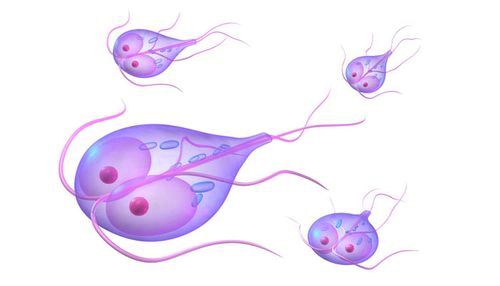

У людському організмі лямблії можуть існувати в двох формах: рухомий, на вегетативної стадії, і нерухомою, у вигляді цист, менш схильних до зовнішніх впливів. Обидві стадії розвитку мікроорганізму однаково небезпечні для здоров'я людини.